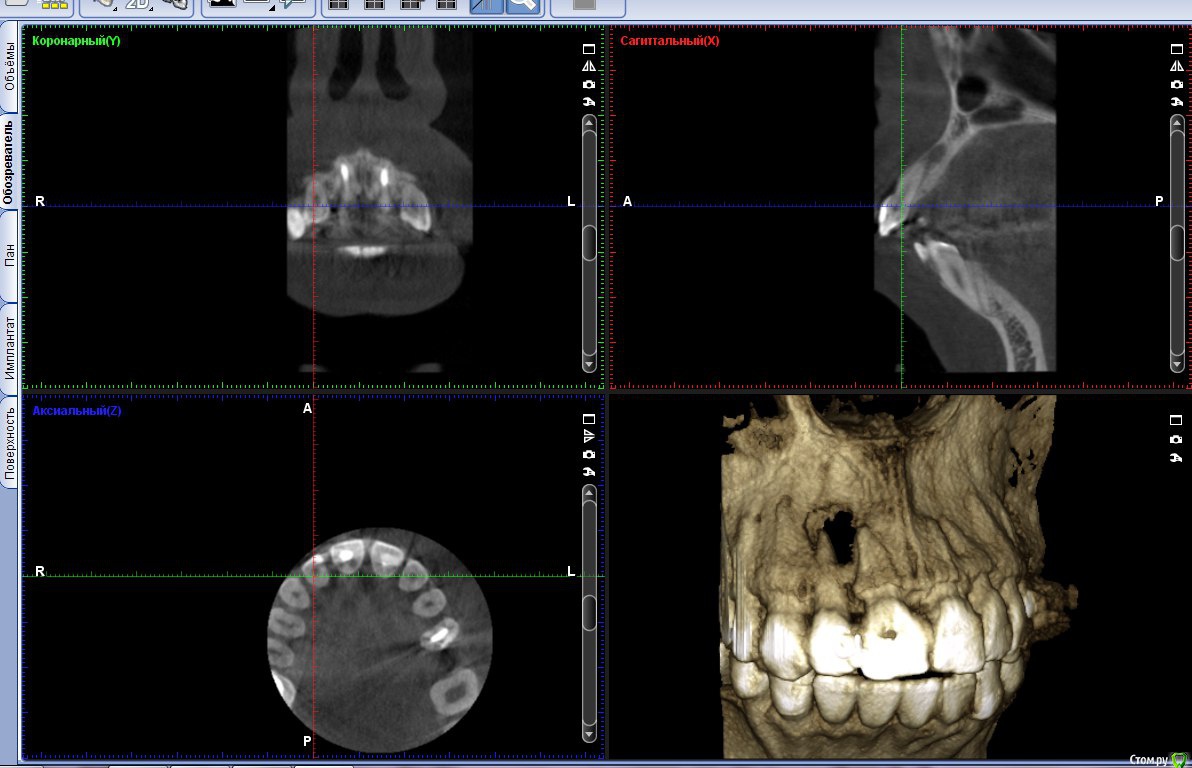

beznika2904 Опубликовано 1 декабря, 2016 Поделиться Опубликовано 1 декабря, 2016 (изменено) Здравствуйте! на этапе подготовки к ортодонтическому лечению обнаружилась большая киста на зубе 1.2, также предстоит операция по изменению открытого прикуса скорее всего на двух челюстях (но один хирург советовал на нижней, а верхнюю изменять только с помощью брекетов), для меня важно как можно быстрее начать ортодонтическое лечение, зуб до этого не лечился, каналы не запломбированы, скорее всего киста появилась из-за давней травмы в детстве соседнего зуба (лет в 12, сейчас мне 22), на данный момент никак не беспокоит, стоит очень крепко в начале хирург говорил что шансы на сохранение зуба очень маленькие, так как киста расположена до половины корня или на еще большей части, что в итоге от корня останется очень маленькая часть и зубу будет тяжело держатьсятакже сказали что отправят мой снимок (прицельный, к сожалению его нет) моему челюстно-лицевому хирургу, он ответил что нужно пытаться спасать зуб, пломбировать канал и делать резекцию части корня вместе с кистой, а перед операцией (можно и до пломбирования) его нужно зашинировать наверно это для того чтобы остался мой зуб для ортодонтического лечения? иначе прикус менять будет сложно, если я правильно понимаю также была на консультации у еще одного хирурга, посоветовал сначала пломбировать каналы, пролечить сам зуб, затем понаблюдать за кистой, так как она находится как я поняла у десны а не вглубь к носу, что возможно она уменьшится после лечения зуба, посоветуйте пожалуйста, как лучше поступить, что вы думаете по этой ситуацииКТ http://my-files.ru/tii9oh, также попыталась сделать скрин Изменено 1 декабря, 2016 пользователем beznika2904 Ссылка на комментарий

beznika2904 Опубликовано 1 декабря, 2016 Автор Поделиться Опубликовано 1 декабря, 2016 Попробуйте найти врача на форуме - http://forum.stom.ru/topic/4752-posovetujte-terapevta-v-gorode-n/написала своему ортодонту, ответил что на его взгляд "киста размером 1,5 см в диаметре не пройдёт и не уменьшится ни от какого лечения"киста и правда большая,не знаю видно ли это на снимке, но я все-таки надеюсь на лечение Ссылка на комментарий